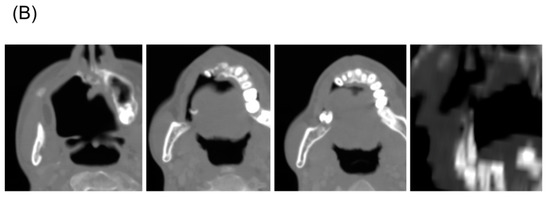

Figure 1.

A representative patient with mucoepimoid carcinoma (yellow arrow) of the hard palate who experienced tooth loss after carbon ion radiotherapy (CIRT) with 64 Gy (relative biological effectiveness) delivered in 16 fractions. (A) Treatment planning computed tomography (CT) images showing isodose lines and the contours of the teeth (the three left-most images are axial sections and the right-most image is a coronal secton). (B) CT images taken 5 years post-CIRT.

The present study enrolled 14 patients (Table 1) and 171 teeth identified on pre-CIRT examination were analyzed. Primary tumor sites were located mainly in the nasal cavity and maxillary sinus, which are adjacent to the maxillary teeth. Adenoid cystic carcinoma was the most common histological type. Most patients received a dose of 64.0 Gy (RBE), delivered in 16 fractions. The median follow-up period was 69.1 months (range, 38.6–96.5 months). During follow-up, loss of 25 teeth was observed. One of the 25 lost teeth was excluded for the analysis because the p-value assessed by the Smirnov–Grubbs’ test was below <0.05 for V10, V20, V30, V40, V50, and V60, suggesting that the loss of this tooth was unrelated to CIRT (Supplementary Figure S1). Figure 1 shows a representative case of tooth loss; at 5 years post-CIRT, a part of the alveolar bone of the maxilla, which received high-dose carbon ions, disappeared and resulted in the loss of four teeth.

In addition to radiation, causes of tooth loss include caries and periodontal disease [30,31,32]. Furthermore, tumor invasion into the maxilla may be a factor that affects tooth loss after treatment. This study did not examine these factors. However, none of the patients lost teeth due to extractions caused by tooth decay in this study. In order to clarify the relationship between the irradiated dose and tooth loss, we excluded patients who did not have irradiated teeth. Of the 25 teeth lost, one was excluded from the analysis because it was clearly an outlier in terms of the irradiated dose; therefore, we assumed that loss of this tooth was caused by factors other than radiation. Regarding loss of the other 24 teeth, we noted that the maxillary bone that supported these teeth disappeared. These changes occurred in line with the distribution of high-dose irradiation in CIRT (Figure 1B) and were uncommon with photon radiotherapy. Clinically, we believe that tooth loss is related to the loss of maxillary bone and evaluated the dose of only the root part and not the crown part in this study. The dosimetric parameters for the root part predicted tooth loss with high accuracy. If factors other than irradiation, such as caries and periodontal disease, had a greater influence, the relationship between dosimetric parameters and tooth loss would not be so clear. Taken together, we consider that factors other than irradiation had a small effect on the loss of the teeth analyzed herein. If these cutoffs can be adhered to, then tooth loss can be prevented in most cases.